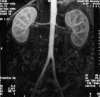

ABC of arterial and venous disease. Non-invasive methods of arterial and venous assessment